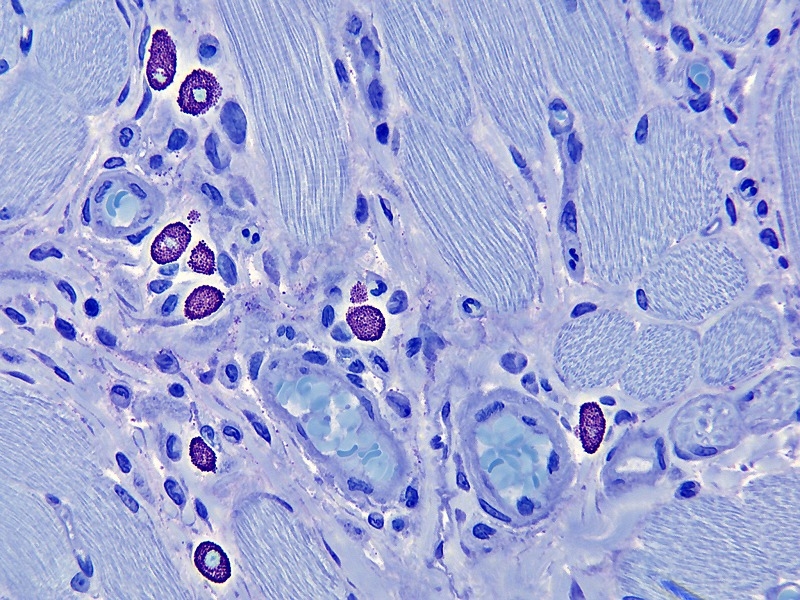

Immer schon habe ich mich gewundert warum in ein meine Maus-Zungenschnitte so viele Mastzellen zu sehen sind. Meine erste Meinung war immer das so was nicht Gans Normal sein muss aber da habe ich mich doch geirrt! Mein letztes Maus Buch gibt da die Antwort. Ist Gans Normal, die gehören da einfach!

Vier Bilder von ein Plastikschnitt.

Farbung: Toluidin Blau;

Objektiv: Leitz Planapo 40x

Kamera: Moticam 2300 am Leitz Orthoplan.

Danke für euren Lob. Ja die Mastzellen bleiben immer mein Favorit, die Farben sich so schon metachromatisch und sind mit die viele scharfe Körnchen immer sehr schon um zu sehen.